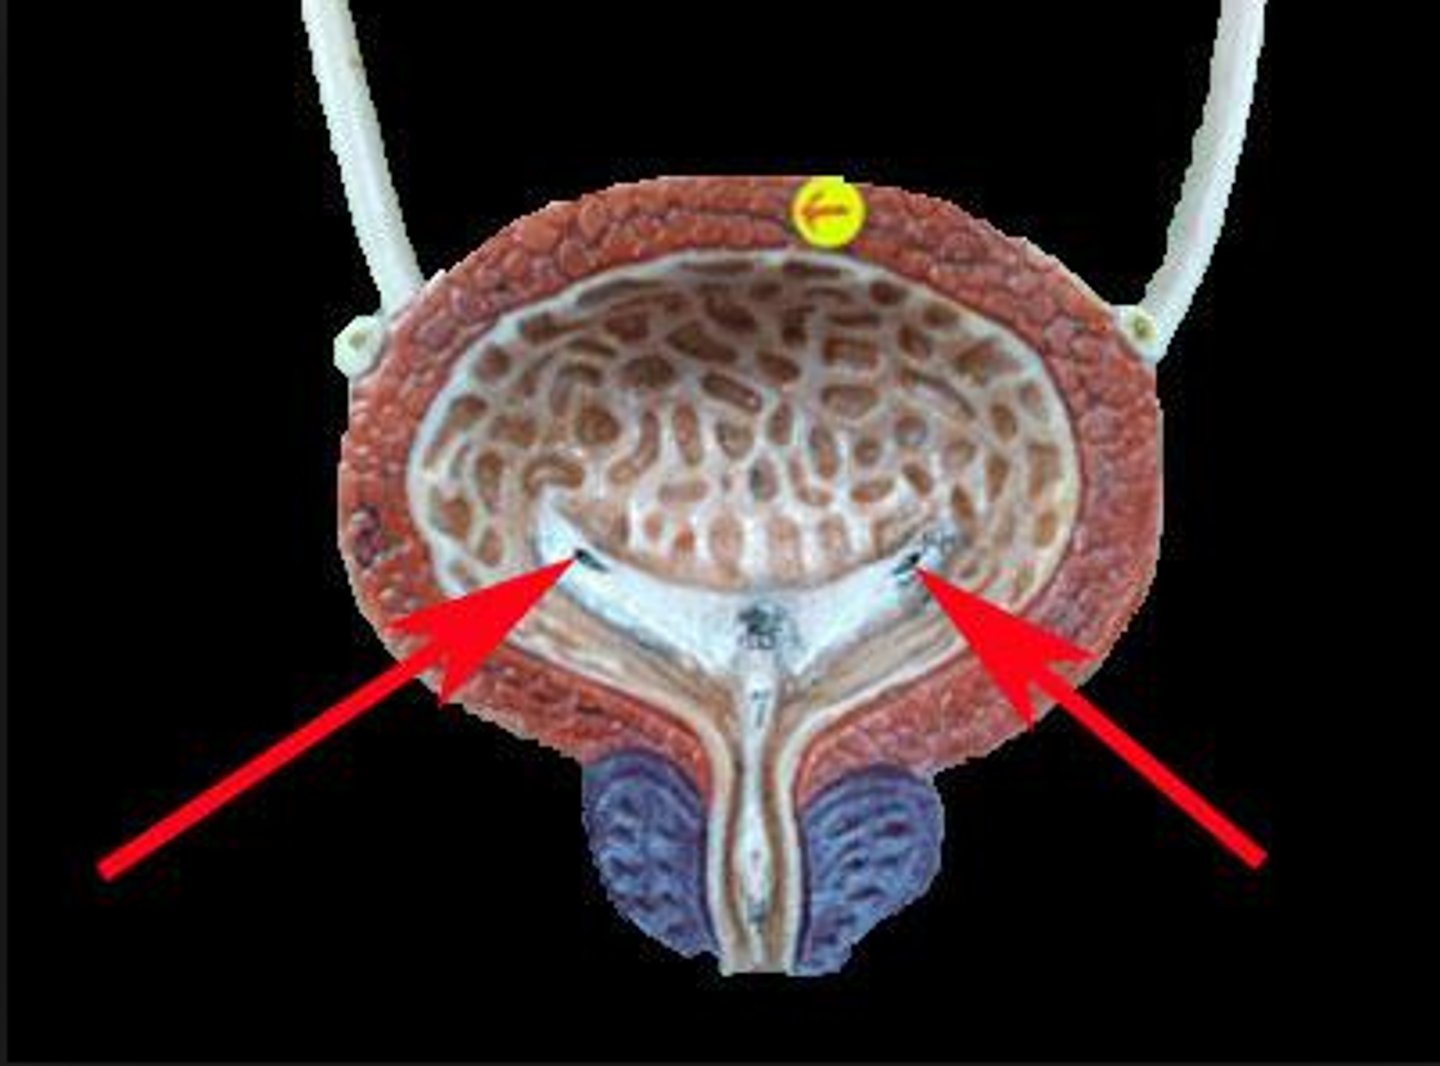

urinary bladder

urinary bladder

detrusor muscle

layer

internal urethral sphincter

bladder neck

external urethral sphincter

ureteric orifice

trigone of bladder

rugae

Urethra